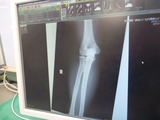

ºòÆü¤ÎROC¤Ë¤Æ2¥³¡¼¥Ê¡¼¤ò¥³¡¼¥¹¥¢¥¦¥È¤·¤Æ·ãÆÍ¤·¤Þ¤·¤¿¡£

¤Û¤Ü¥Î¡¼¥Ö¥ì¡¼¥¤Ç

ÀµÌ̤«¤é´Ë¾×ºà¤Ë·ãÆÍ¤·¤Þ¤·¤¿¡£

¤½¤Î¤Þ¤ÞÎ뼯¥µ¡¼¥¥Ã¥È¤Î¥á¥Ç¥£¥«¥ë¤Ë¤Æ

¿Ç»¡¤ò¼õ¤±¤Æ¡¢ËÜÆü¼ç¼£°å¤Î¿Ç»¡¤ò¼õ¤±¤Þ¤·¤¿¡£

¹¬¤¤¤Ê»ö¤Ë¹ü¤Ë°Û¾ï¤Ï̵¤¯°ì°Â¿´¤Ç¤¹¤¬

¶¯Îõ¤ÊÁ´¿ÈÂÇËФÈ

±¦¤Ò¤¸¤¸¤óÂÓ»½ý¤Ç

Á´¼£2½µ´Ö¤ÎÆþ±¡²ÃÎŤò¿ÇÃǤµ¤ì¤Þ¤·¤¿¤¬

Æþ±¡·ù¤¤¤ÎËͤλö¤òʬ¤«¤Ã¤Æ¤¤¤ë

¼ç¼£°å¤ÎȽÃǤˤơ¢Ìµ»ö¤Ë³«Êü¤µ¤ì¤Þ¤·¤¿¤¬

¤¢¤Þ¤ê¤Î·ãÄˤ椨¡¢Ä̾ï¶È̳¤¬½ÐÍè¤ë¾õÂ֤ǤϤʤ¤¤Î¤Ç

»Ã¤¯¤Î´Ö¡¢»ö̳½èÍý¤Ê¤É¤·¤«½ÐÍè¤Þ¤»¤ó¡£